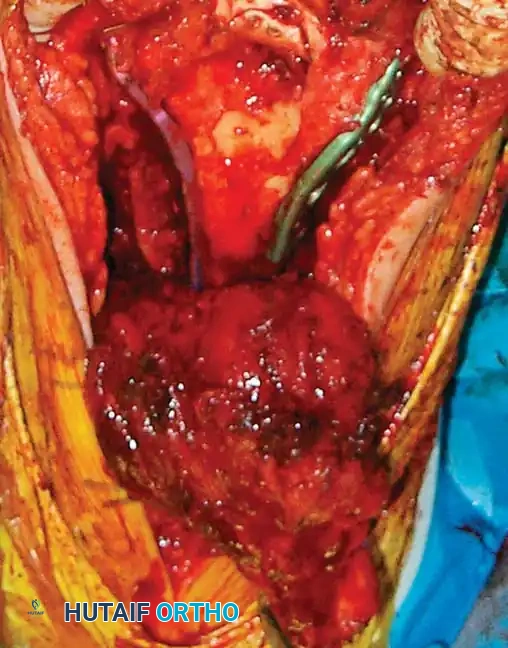

Step-by-Step Reconstruction Strategy

Reconstruction of the distal humerus generally follows one of two strategic pathways, depending on the fracture morphology:

Strategy 1: Articular-First Reconstruction

1. Reduce and provisionally fix the articular fragments (trochlea and capitellum) to each other using K-wires.

2. Convert provisional fixation to definitive fixation using headless compression screws or countersunk lag screws.

3. Reduce the reconstructed articular block to the humeral metaphysis/diaphysis.

4. Apply bicolumnar plating.

Image

Fig. 12: Intraoperative view demonstrating provisional K-wire fixation of the articular block prior to metaphyseal attachment.